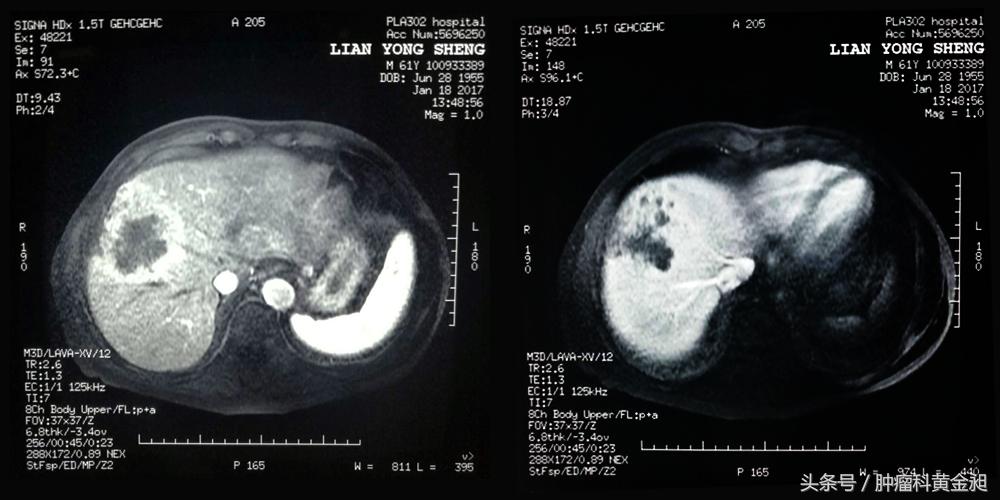

2016年12月确诊肝癌,于某三甲医院行介入栓塞治疗后并未好转,术后一月复查肿瘤无坏死、继续增大,肿瘤由治疗前的4.8*3.8cm和1.0*0.6cm增大到7.2*5.6cm和1.5*0.9cm,且栓塞后综合征反应强烈,患者非常痛苦。

2017年1月22日,就诊于我科室,此时复查肿瘤已增大到9.4*5.9cm,于2017年1月25日由我科室副主任李睿行介入化疗栓塞治疗,术后肿瘤的供血血管被堵塞,肿瘤血管染色消失,术后24小时,肿瘤开始坏死,患者出现高热,39.0℃,但患者无寒颤,为典型的吸收热表现。查体示患者脉弦,故李大夫采取耳尖放血以泻热祛邪,后背膀胱经走罐以疏通经络,支沟穴、阳陵泉下3寸针刺以理气,并配合火针围剿抑瘤等中医特点疗法,金匮统元方加减以改善食欲,健运脾胃。患者术后体力恢复迅速,栓塞后综合征的各种反应很快就消失了。两周后复查CT,显示肿瘤坏死,缩小。

术前影像

患者术后恢复迅速,复查肿瘤区域坏死,缩小